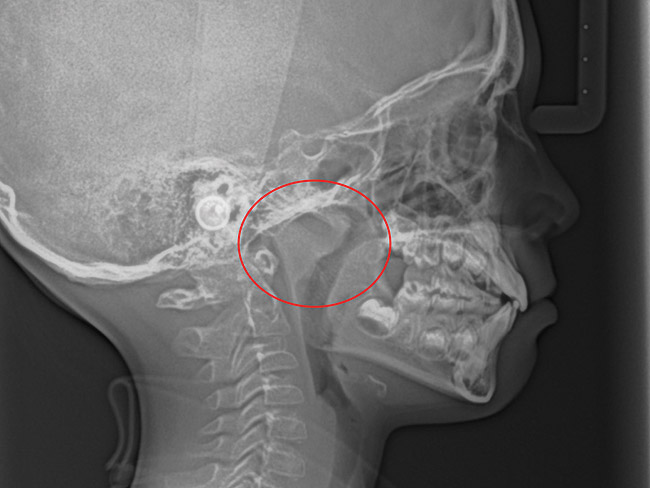

(15.) Cephalometric evaluation demonstrates significant tonsillar blockage of the airway and bimaxillary retursion.

Figure 15